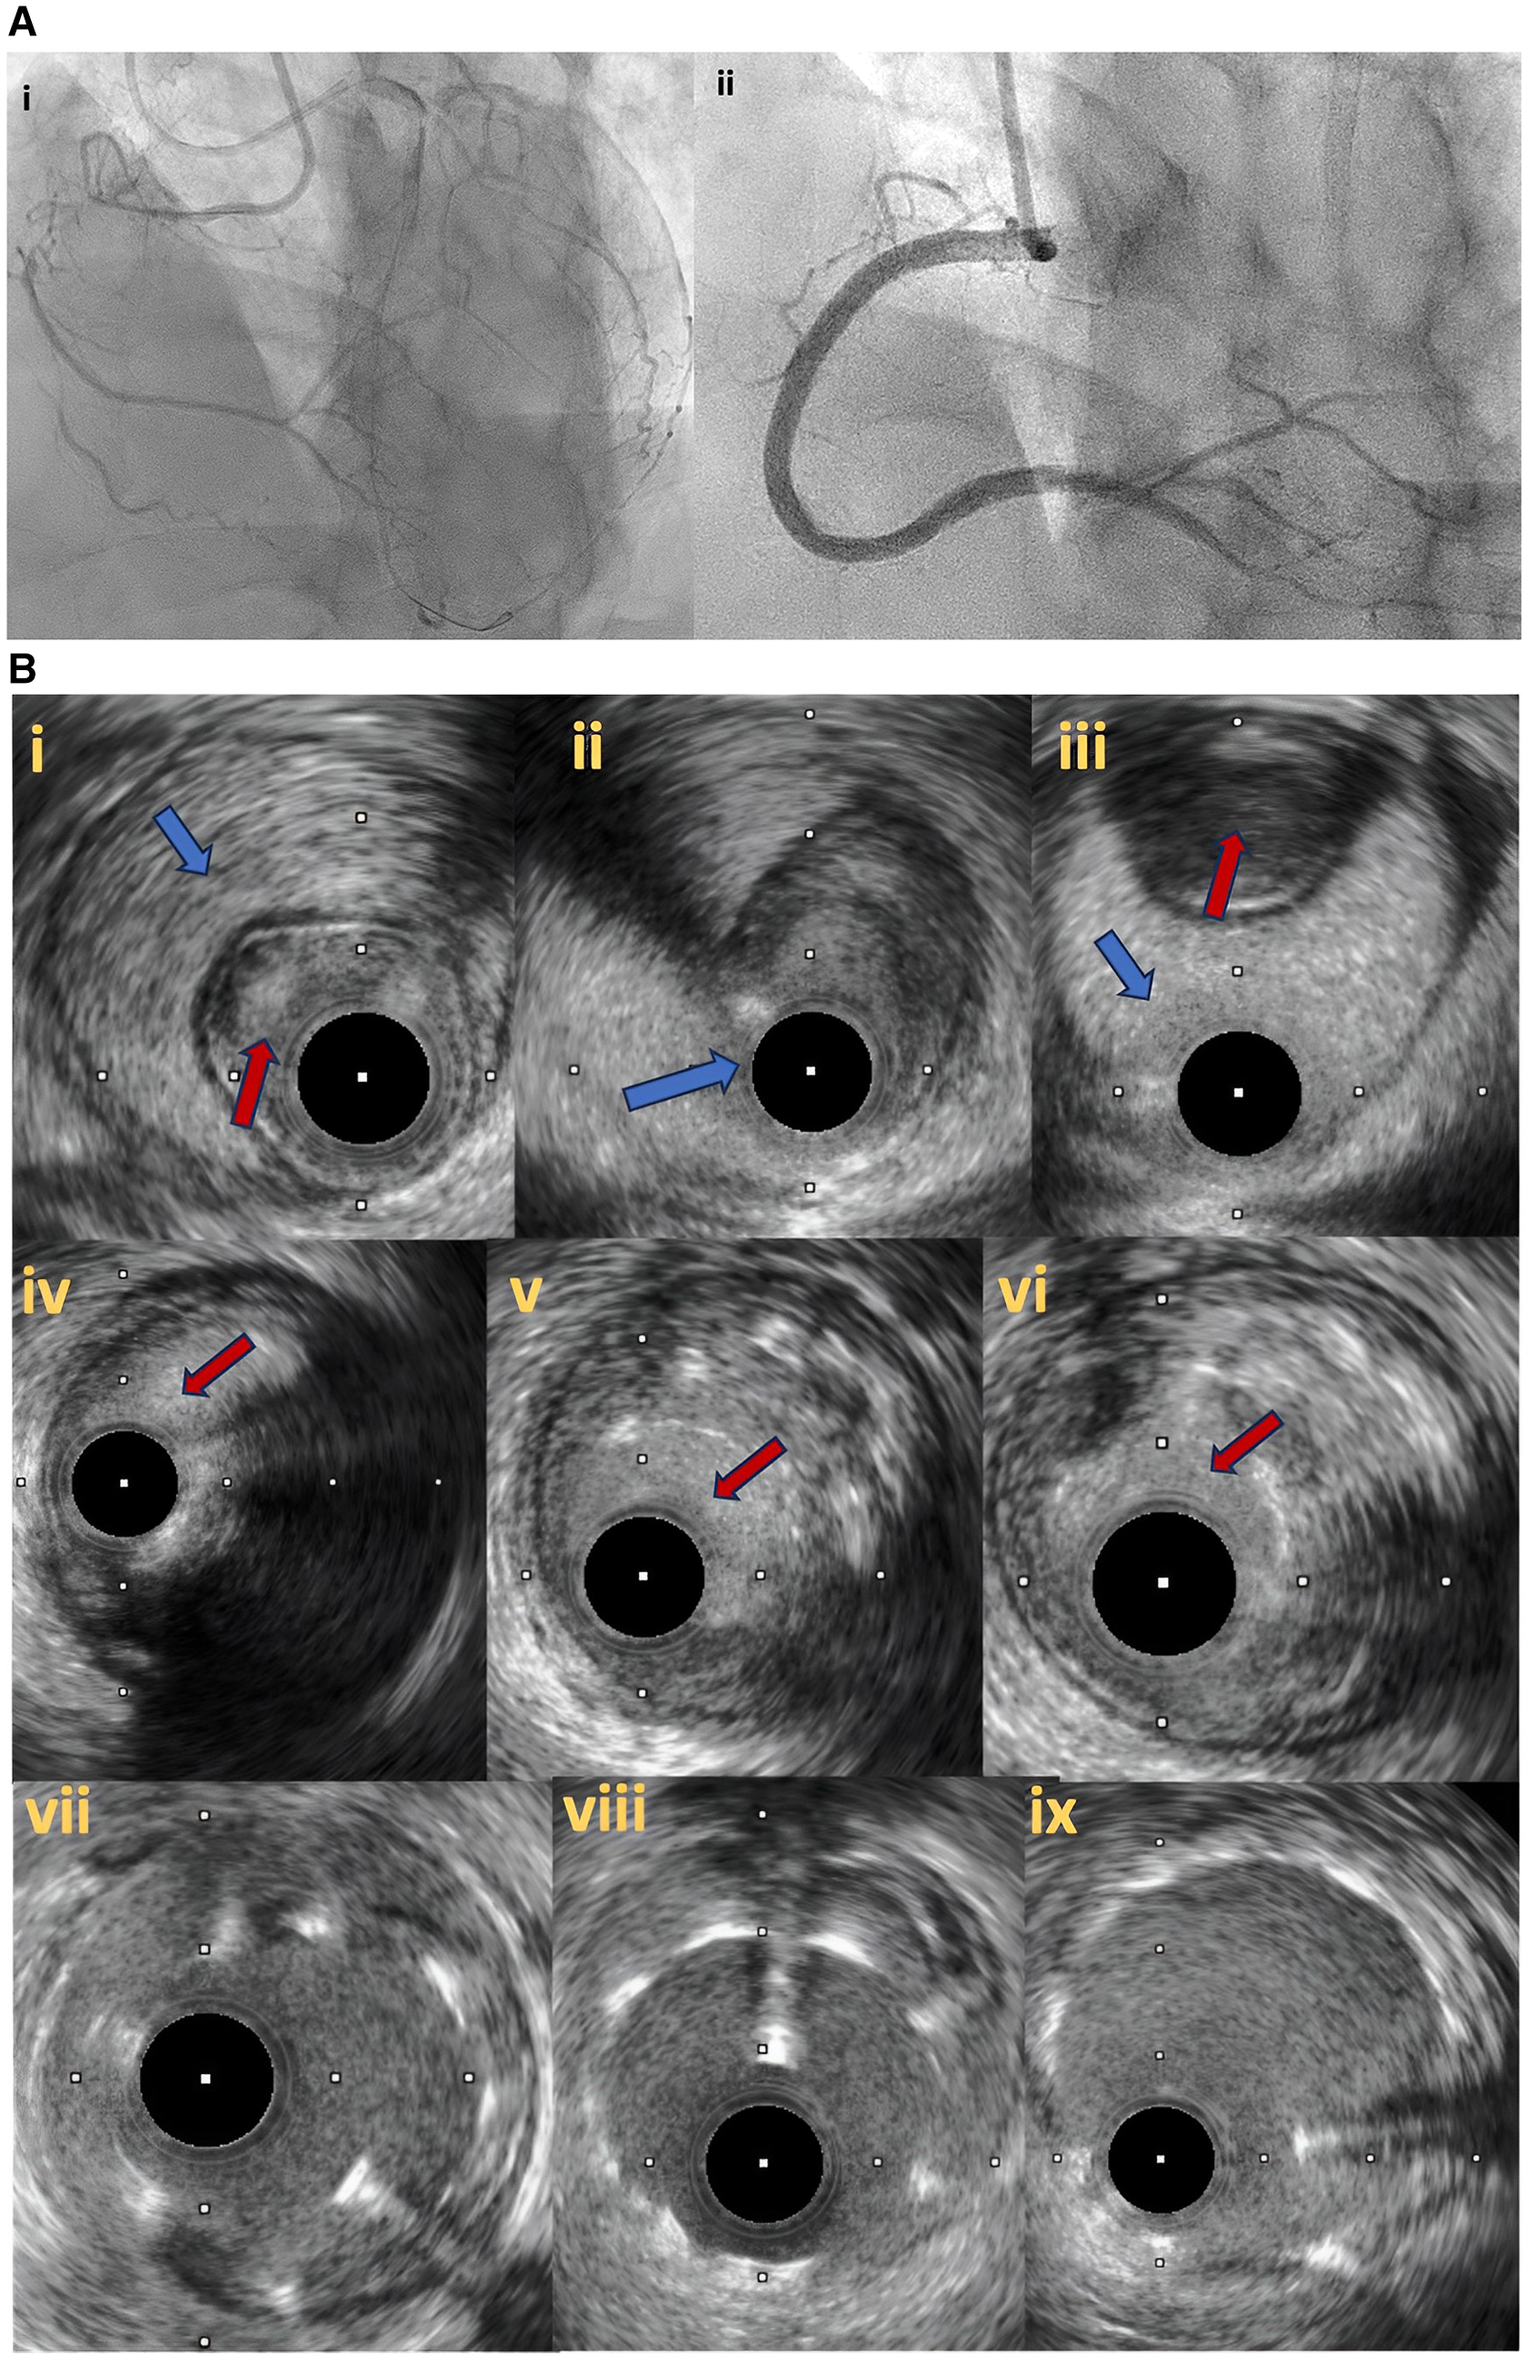

Figure 7

(A) Right coronary artery total occlusion revascularization with antegrade dissection reentry technique (7Ai–ii). (B) Intravascular ultrasound pictures after successful distal true lumen reentry and CTO recanalization. In (7Bi), intraluminal wire position (red arrow) with large subintimal haematoma is noticed. In (7Bii), the transition from true lumen into subintimal space is noticed (blue arrow), whilst in (7biii) the wire is in the subintimal space (blue arrow) that compresses the true lumen (red arrow). In (7Biv–vi), intraplaque wire tracking is noticed. Final IVUS images after stent deployement (7bvii–ix).

Figure 8

Follow up angiography in patient illustrated in figure 7, 3 months after successful RCA CTO PCI (8i). IVUS demonstrates significant stent vessel size mismatch and significant malapposition due to subintimal haematoma healing and vessel positive remodeling after successful PCI (8ii–iv). Angiographic (8v) and IVUS images (8vi–viii) after stent optimization to correct stent-vessel size mismatch and malapposition.